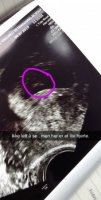

8+3 idag

Ser jo ut som en liten bebi joVis vedlegget 303208 Alt fint på tul i dagTermin stemte meget godt med hva jeg hadde regnet ut selv, 10+6 i dag

Sammenliknet med uke 7. Nå gleder jeg meg masse til TUL nr 2 når jeg er 13 uker på vei!Ja. Ganske mye som skjer på kort tid. Forrige svangerskap var vi ca 1 uke tidligere. Så litt ut som en baby da også, men ikke like godt som denne gangenSer jo ut som en liten bebi joSammenliknet med uke 7. Nå gleder jeg meg masse til TUL nr 2 når jeg er 13 uker på vei!